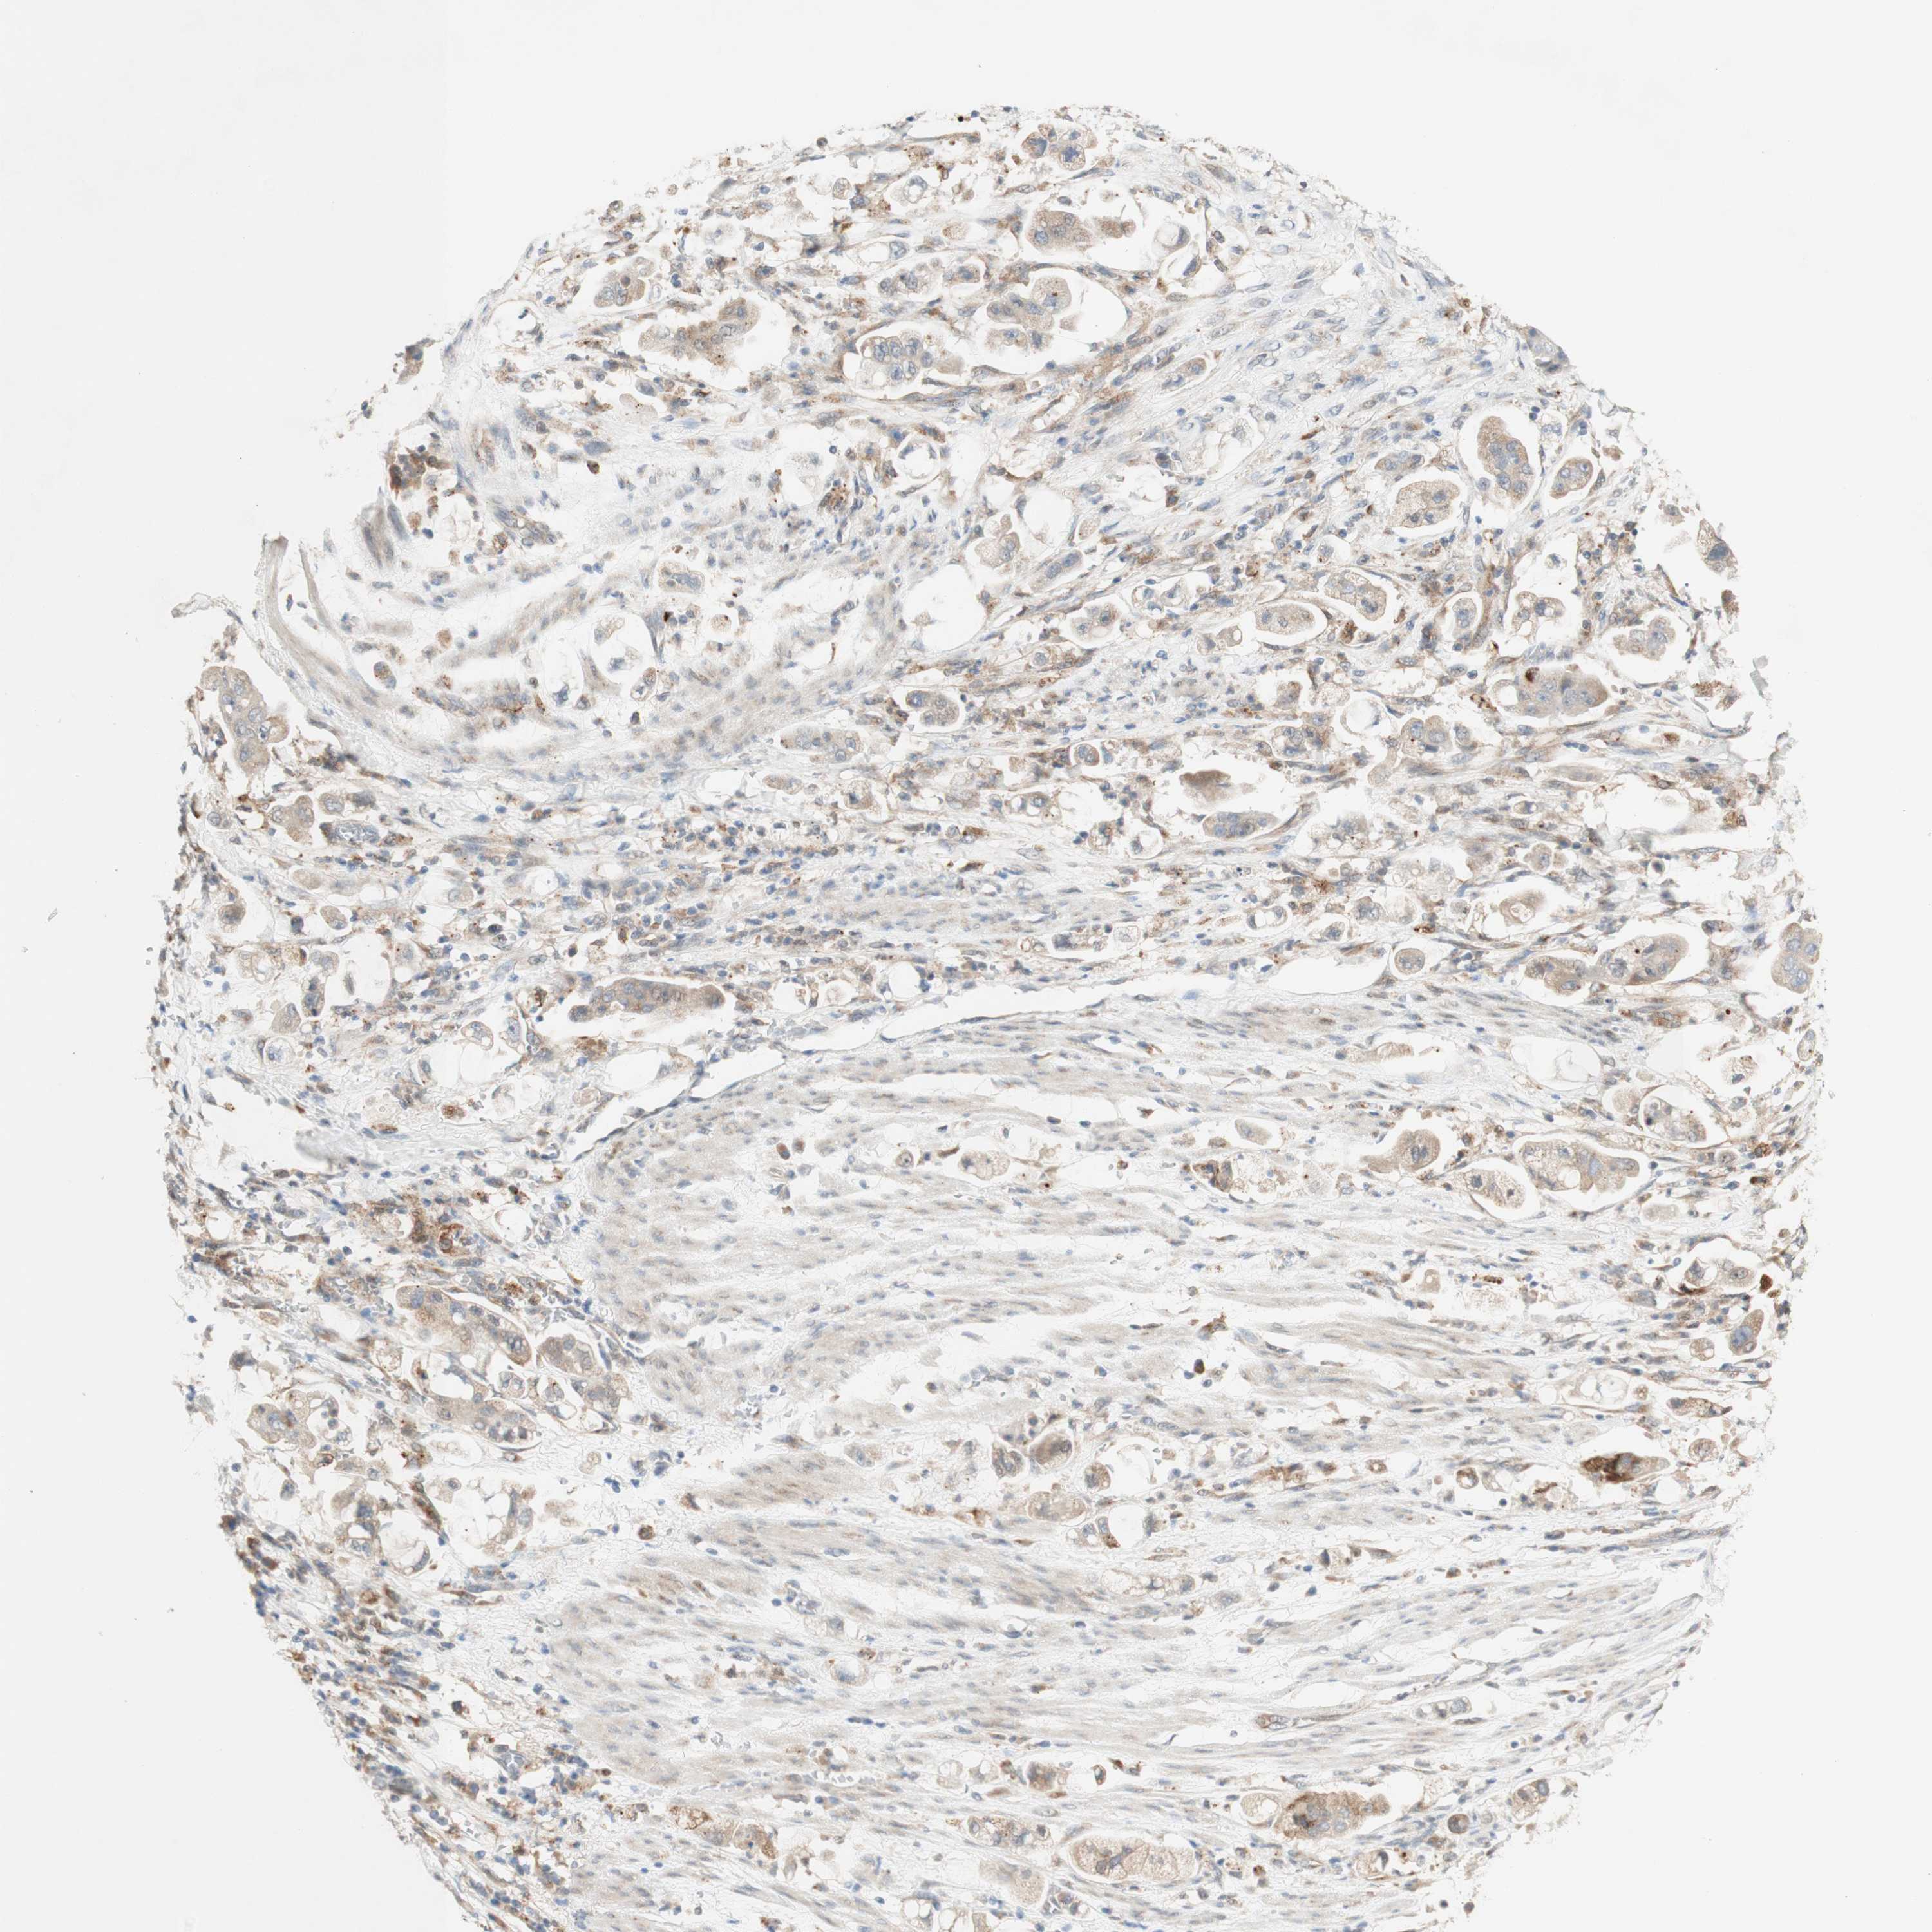

STOMACH CANCER - Protein expressioni

A mouse-over function shows sample information and annotation data. Click on an image to view it in a full screen mode. Samples can be filtered based on level of antibody staining by selecting one or several of the following categories: high, medium, low and not detected. The assay and annotation is described here.

Note that samples used for immunohistochemistry by the Human Protein Atlas do not correspond to samples in the TCGA dataset.

Antibody stainingi

Antibody staining in the annotated cell types in the current human tissue is reported as not detected, low, medium, or high, based on conventional immunohistochemistry profiling in selected tissues. This score is based on the combination of the staining intensity and fraction of stained cells.

Each image is clickable and will lead to virtual microscopy that enables deeper exploration of all samples and also displays staining intensity scores, fraction scores and subcellular localization as well as patient and tissue information for each sample.

Antibody HPA011070

Staining

High

Medium

Low

Not detected

Intensity

Strong

Moderate

Weak

Negative

Quantity

>75%

75%-25%

<25%

None

Location

Nuclear

Cytoplasmic/membranous

Cytoplasmic/membranous,nuclear

Adenocarcinoma, NOS

Adenocarcinoma, High grade